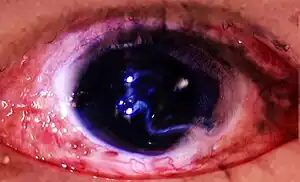

| Globe rupture with visible aqueous leaking from the eye | |

During a globe rupture, the outer membranes of the eye are completely or partially compromised, and the vitreous and/or aqueous humour drain through the site of the rupture, causing the eye to 'deflate'.

Globe rupture

Globe rupture -